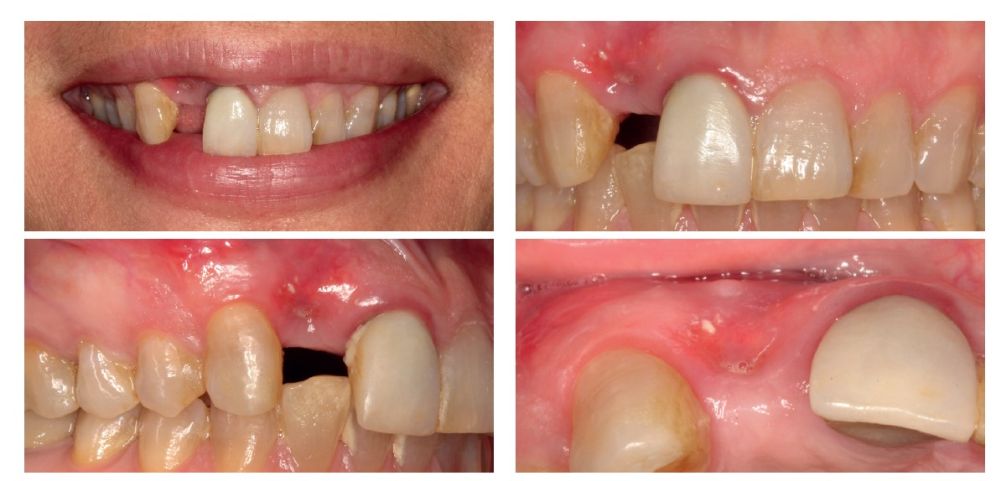

We present the case of a 36-year-old woman who comes to the clinic demanding solution for an implant located in position 1.2. This implant has carried a rehabilitation with a crown for a short period of time in which an important mucositis and loss of the thickness of the gingival tissue occurred, for which the crown was removed. The patient has a provisional removable crown and the soft tissue surrounding the area of the initial emergency of the implant-supported prosthesis is in bad condition, with a significant loss of thickness and the remains of a soft tissue fistula (Figures 1-4).

Four months later, a new dental cone-beam is performed to quantify the gain obtained in width with the regenerative procedure. It is observed in the sectional cut that a crest width of more than 7 mm and a complete regeneration of the alveolar ridge has been achieved, allowing the insertion of a new dental implant in the adequate position (Figure 10). In the surgical reentry, the information of the Cone-Beam is verified with a total integration of the graft material, as shown in the clinical images at the time of lifting the flap for the insertion of the implant (Figures 11 and 12). The microscrew is removed and the implant is placed, which is performed by vestibular compression of the graft to gain in this manner even more contour in this area (Figure 13). The implant is left in a surgical phase, with a low healing abutment that allows a subsequent location of the same without an aggressive soft tissue surgery when the construction of the prosthesis is initiated. The provisional crown remains as an extension from the tooth 1.1.

Three months later, the prosthetic phase begins. The state of the gingival tissue is correct, although at vestibular level we would like to achieve a decrease of the zenith of the future tooth, so a connective tissue graft is planned that allows this more appropriate emergence profile conformation. The case ends with E-max crowns at the level of 1.2 and 1.1, achieving a harmonious smile and fully integrated in the rest of the smile, regarding colour, emergence and disposition of the gingival margins (Figures 14-15). The patient continues a follow up for years, maintaining the stability of the performed rehabilitation (Figure 16).